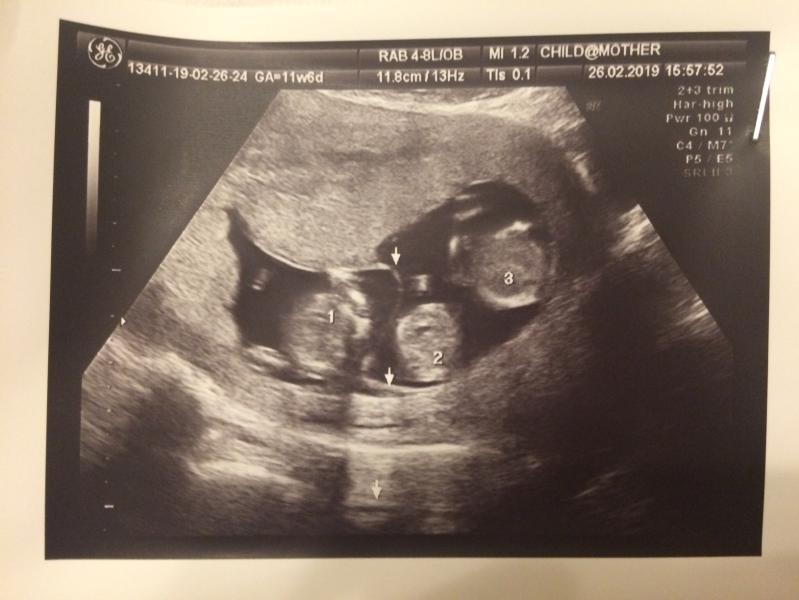

«КАК МЫ УЗНАЛИ О ТРОЙНЕ»)))

26 февраля 2019г.

- двойня? Я направилась к кабинету, захожу, ложусь...начинается опять осмотр, и тут врач опять: ой! Так тут тройня! Здесь я уже не выдержала, началась паника, я стала звать мужа.. говорю: позовите его я сейчас с ума сойду, слезы ручьём, трясусь... заходит Егор с Платоном на руках, улыбается))), смотрит на меня рыдающую, потом на экран и тут ему говорят: ну что папочка, у вас тройня! Выражение лица моего мужа я ещё таким никогда не видела, глаза большие... говорю ему сквозь слезы: не урони Платона! Спрашиваю: у тебя в роду такое было? Он: нет! Я ему: и у меня нет! Как так...? Может это все НСП ? Немного успокоившись и взяв результаты узи мы пошли на выход... в таком немного шоковом состоянии мы прибывали долго, я так до сих пор ещё не могу привыкнуть к тому, что стану сразу многодетной мамой 4 детей))).